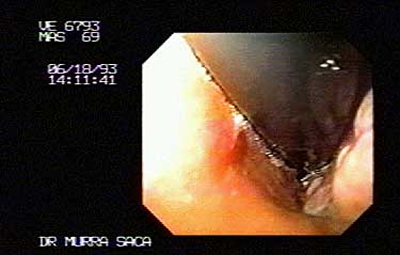

Imagen del cardias, Paciente Masculino 69 años:

Con disfagia progresiva, perdida de peso 20 libras y sialorrea, presenta Carcinoma del cardias y fondo, ver imagenes siguientes.

-

Fondo por retroflexión, mismo paciente de fotografía anterior: